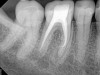

Fig 4.  Due to reported allergies to resin-based materials and eugenol, obturation was completed with a calcium hydroxide-based sealer (Figure 4 and Figure 5) with healing noted at a 1-year follow-up (Figure 6).

Figure 4

Fig 5.  Due to reported allergies to resin-based materials and eugenol, obturation was completed with a calcium hydroxide-based sealer (Figure 4 and Figure 5) with healing noted at a 1-year follow-up (Figure 6).

Figure 5

Fig 6.  Due to reported allergies to resin-based materials and eugenol, obturation was completed with a calcium hydroxide-based sealer (Figure 4 and Figure 5) with healing noted at a 1-year follow-up (Figure 6).

Figure 6